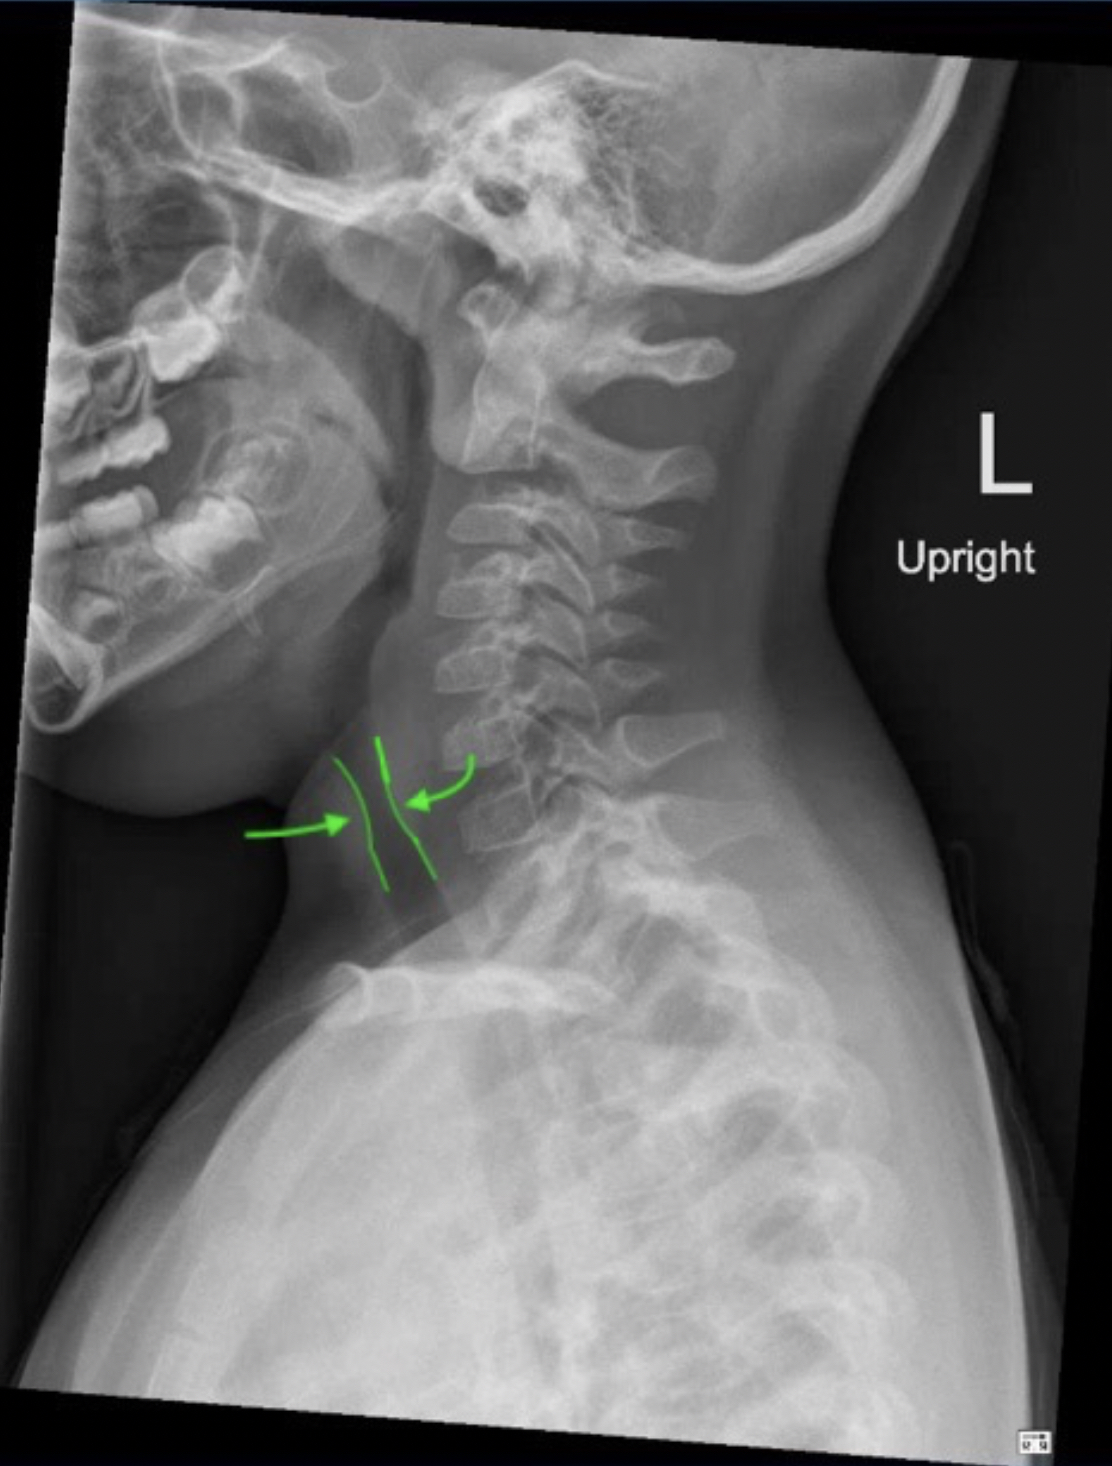

• El estridor es un ruido de tono alto, sobre todo inspiratorio. Se asocia con mayor frecuencia con trastornos agudos, como aspiración de cuerpo extraño, pero puede deberse a trastornos más crónicos, como traqueomalacia.

• El estridor se produce por el flujo de aire rápido y turbulento a través de un segmento estrechado o parcialmente obstruido de la vía aérea superior extratorácica. Las áreas afectadas son la faringe, la epiglotis, la laringe y la tráquea extratorácica.